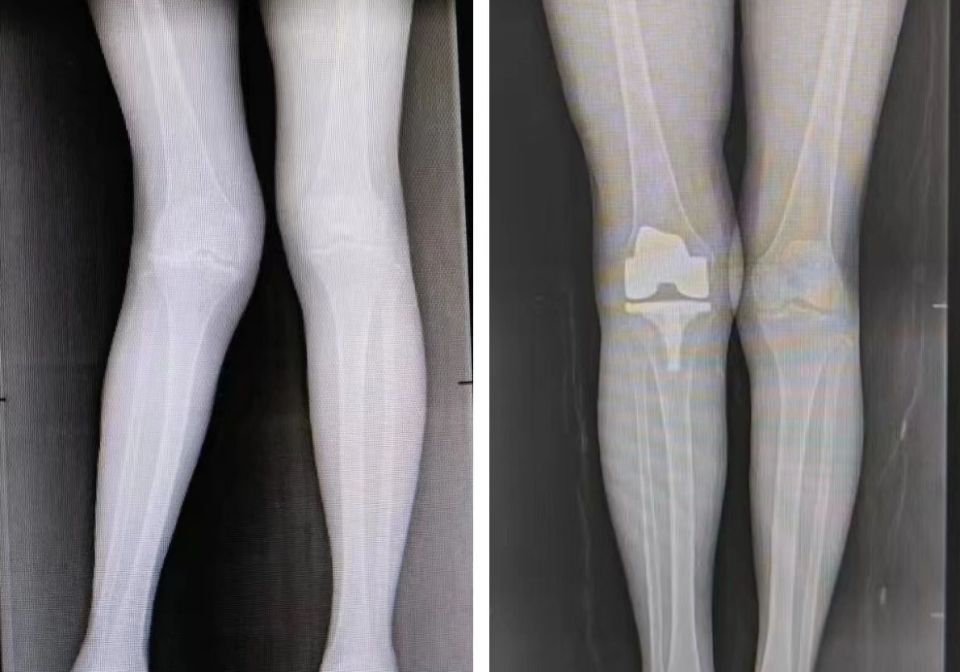

术前术后对比,右膝关节外翻畸形已矫正膝关节外翻畸形已矫正,常规关节

图片尺寸960x672